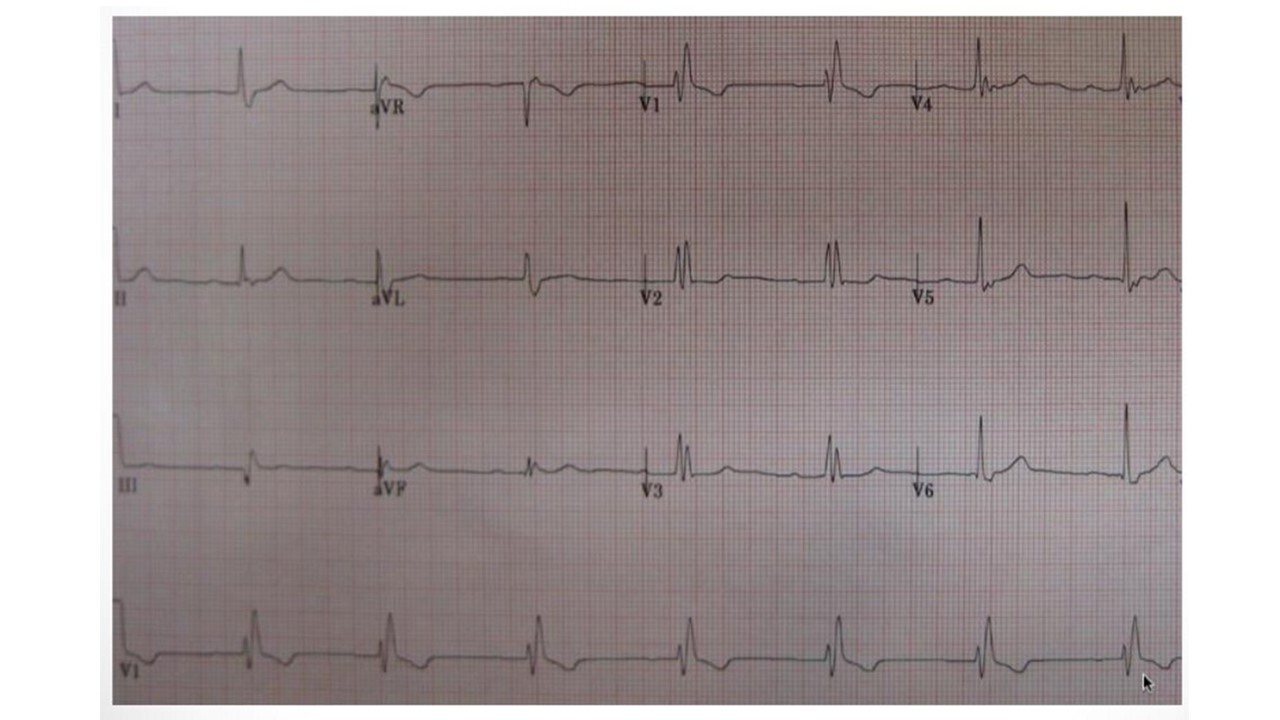

21

LBBB